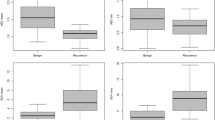

Associations of imaging parameters per subgroup

Seventy PT ROIs were drawn and 59 lymph node metastasis ROIs (largest LNM) on each modality (Table 1). The comparison of both observers resulted in no significant different values and a high interobserver correlation (Supplement 1). A Dice index in primary tumors of 0.88 at the DWI/IVIM and 0.85 at DCE delineation was found (not tabulated). For LNM, a Dice index of 0.97 at DCE and 0.92 at DWI/IVIM delineation was found (not tabulated). Primary tumor ADCGTV, D, f, and D*, DCEGTV, and all 18F-FDG-PET values (Supplement 2) were significantly higher in advanced T-staged tumors (all p ≤ 0.02). In advanced N-staged tumors, PT ADCGTV and Ve were significantly higher (p = 0.021 and p = 0.023, respectively). In HPV-negative tumors, ADCmean, D, D*, SUVmax, SUVmean, and SUVpeak were significantly higher than HPV-positives (p < 0.043). In patients with intoxications, ADCmean, D, and D* were significantly different among the different categories (all p < 0.027).

In LNM (Supplement 3), Kep and all 18F-FDG-PET parameters were significantly higher in advanced N-stages (p = 0.025, p ≤ 0.016, respectively). In HPV-negative tumors, D was found to be significantly higher (p = 0.002) and D* lower (p = 0.007) than in HPV-positive tumors. In patients with intoxications, f was found to be significantly lower (p = 0.026).

Primary tumor univariate analysis (Table 3) showed that clinical parameters HPV status, PT location, intoxications (p ≤ 0.047), and imaging parameters ADCGTV, ADCmean, D*, D, DCEGTV, Ve, MATV, and SUVmax, were significantly associated with OS (all p ≤ 0.047). For LNM, SUVmax, SUVmean, and SUVpeak were associated with OS (all p ≤ 0.015).

In multivariate analysis per single modality (Table 3), corrected for clinical parameters (i.e., HPV status, hypopharyngeal PT location, intoxications), ADCGTV (p = 0.004), D* (p = 0.016), DCEGTV (p = 0.001), Ve (p = 0.019), MATV (p = 0.088), and SUVmax (p = 0.001) remained predictive for OS. In LNM, only SUVmax (p = 0.055, HR = 0.563) and SUVmean (p = 0.005, HR 3.536) remained predictive for OS. The subgroup analysis in HPV-negative patients is shown in Supplement 7.

The multivariable CoxBoost analysis combining all PT parameters of all modalities, including all clinical parameters (Table 4), shows that N-stage, HPV status, PT location, intoxications, PT ADCGTV, ADCmean, D*, Ktrans, Ve, SUVmax, and TLG remain predictive for OS, with a C-index of 0.664.